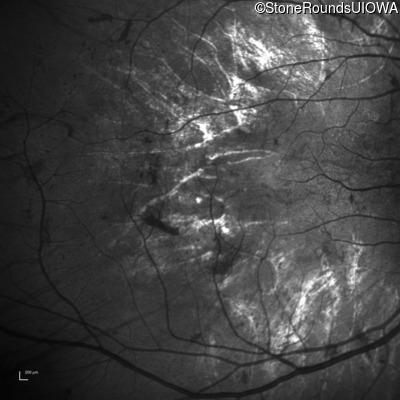

Infrared Fundus Photograph - Right - 20/200 -1

Exemplar